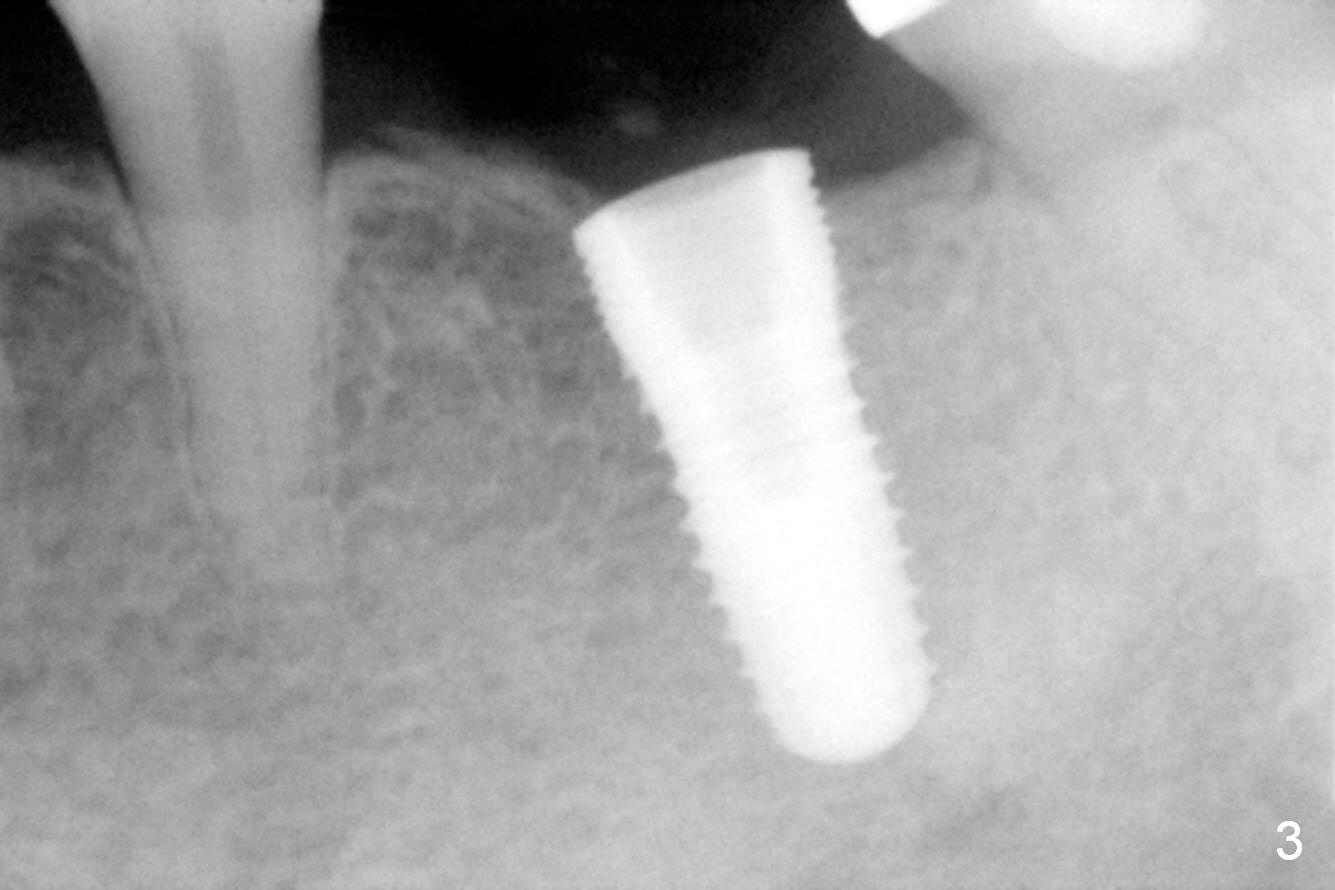

The edentulous ridge at #19 is moderately wide at the base, but pointed at the crest (Fig.1). After raising flaps, it appears that the ridge can hold a 5 mm implant using an implant positioner. The initial osteotomy is 12 mm deep and about 4 mm from the Inferior Alveolar Canal (Fig.2 yellow dashed line). Sequential osteotomy is carried out until 5x12 mm. Because of the pointed crest, 4.5 drill is used to extend the osteotomy at ~ 13 mm so that 12 mm implant can be placed a little deeper to reduce the amount of thread exposure. A 5.3x12 mm implant cannot be seated as deep as expected. A 5.3x10 mm drill with stopper is used before placing the same implant as mentioned above at the desirable depth (Fig.3). The insertion torque is > 60 Ncm. An abutment is placed immediately and an immediate provisional is fabricated and seated. Two to 3 microthreads buccally and lingually are covered by autogenous bone graft and collagen membrane. The patient returns for impression 4 months postop. There is bone loss distally (Fig.4 *). His oral hygiene is excellent. It is hoped that the bone loss will not get worse in the next visit.